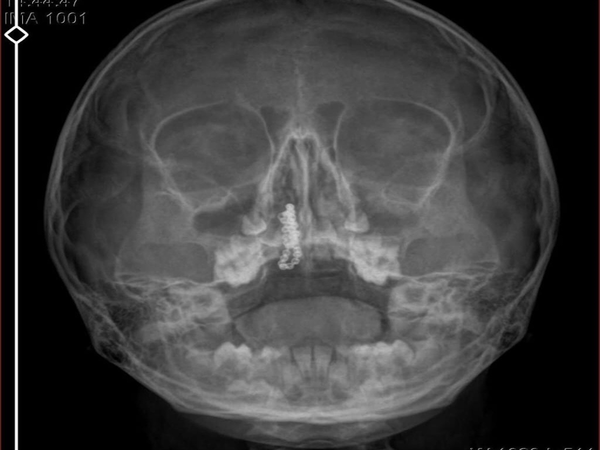

Eve dönen aile, kanama ve akıntının geçmemesi üzerine bu kez Rize Devlet Hastanesi'ne giderek Kulak Burun Boğaz Polikliniği'ne başvurdu. Devlet hastanesindeki doktorun incelemesi ve kapsamlı röntgen çekilmesi sonrası Polen'in burnunda metal cisim olduğu fark edildi.

2 yıldır burunda kaldığı değerlendirilip, küçük top şeklinde tırnak makası zinciri olduğu belirlenen cisim, başarılı ameliyatla çıkarıldı. Bir süre tedavisi sürdürülen Polen, sağlığına kavuşunca taburcu edildi. Özel hastane yetkilileri, konuyla ilgili açıklama yapmazken; aile suç duyurusunda bulunacaklarını söyledi.